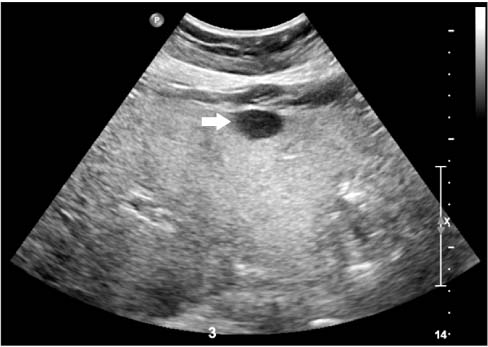

Abdominal ultrasonography showed a fatty liver with a 1.6-cm well-defined nodule (Fig. 1). Computed tomography revealed an enhancing nodule in the arterial and delayed phases. Magnetic resonance imaging showed a nodule with atypical enhancing pattern and low signal intensity in the hepatobiliary phase (Fig. 2). These findings did not suggest liver cirrhosis or specific HCC findings. So, we performed a liver needle biopsy for an accurate diagnosis. A liver needle biopsy demonstrated well-differentiated HCC within NASH background. The patient had a Child-Pugh score of 6, and the indocyanine green test result was 20.1% (range, 0% to 10%). The patient underwent segmentectomy of segment III, as remnant liver function was good. Grossly, a 1.9×1.5 cm sized nodular mass was noted. Microscopically, the mass revealed small, progressed HCC without vascular or lymphatic invasion. Non-tumor parenchyma showed findings consistent with NASH (Fig. 3). Also, HBcAg was not detected in the liver parenchyma. The patient had a successful operation without complications and is being followed-up for 9 months without evidence of recurrence.

Fig. 1

Abdominal ultrasonography. It shows a 1.6 cm size well-defined hypoechoic nodule in liver segment III (arrow).

Fig. 1 Abdominal ultrasonography. It shows a 1.6 cm size well-defined hypoechoic nodule in liver segment III (arrow).